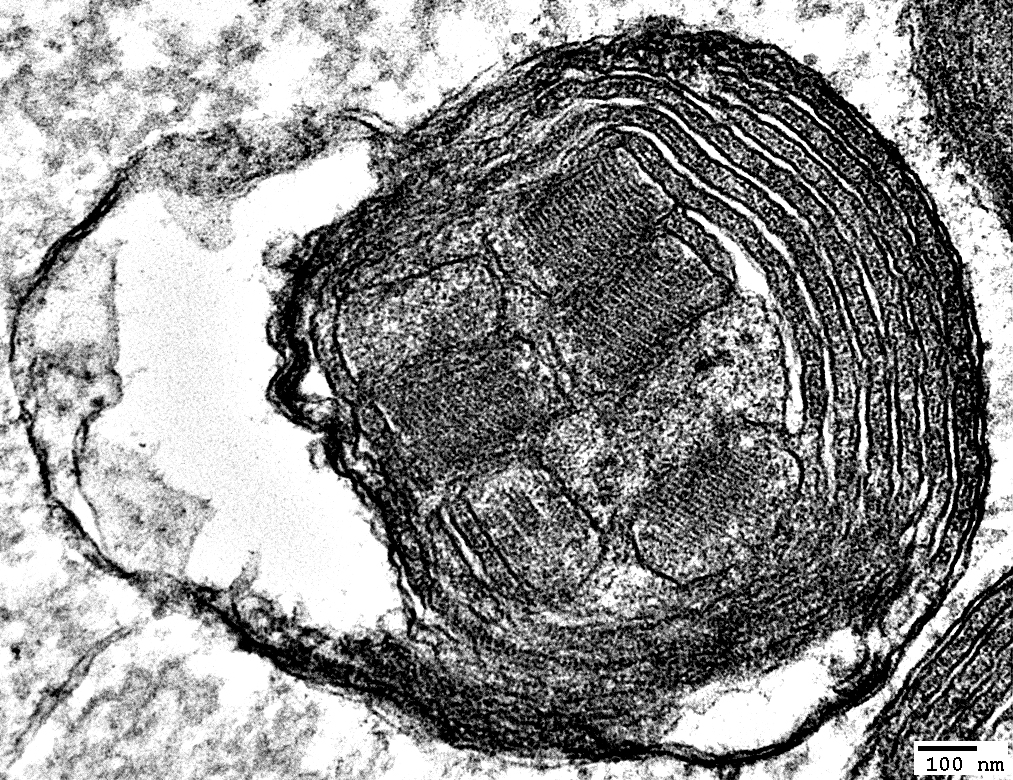

MNGIE: Muscle Ultrastructure

From: R Schmidt